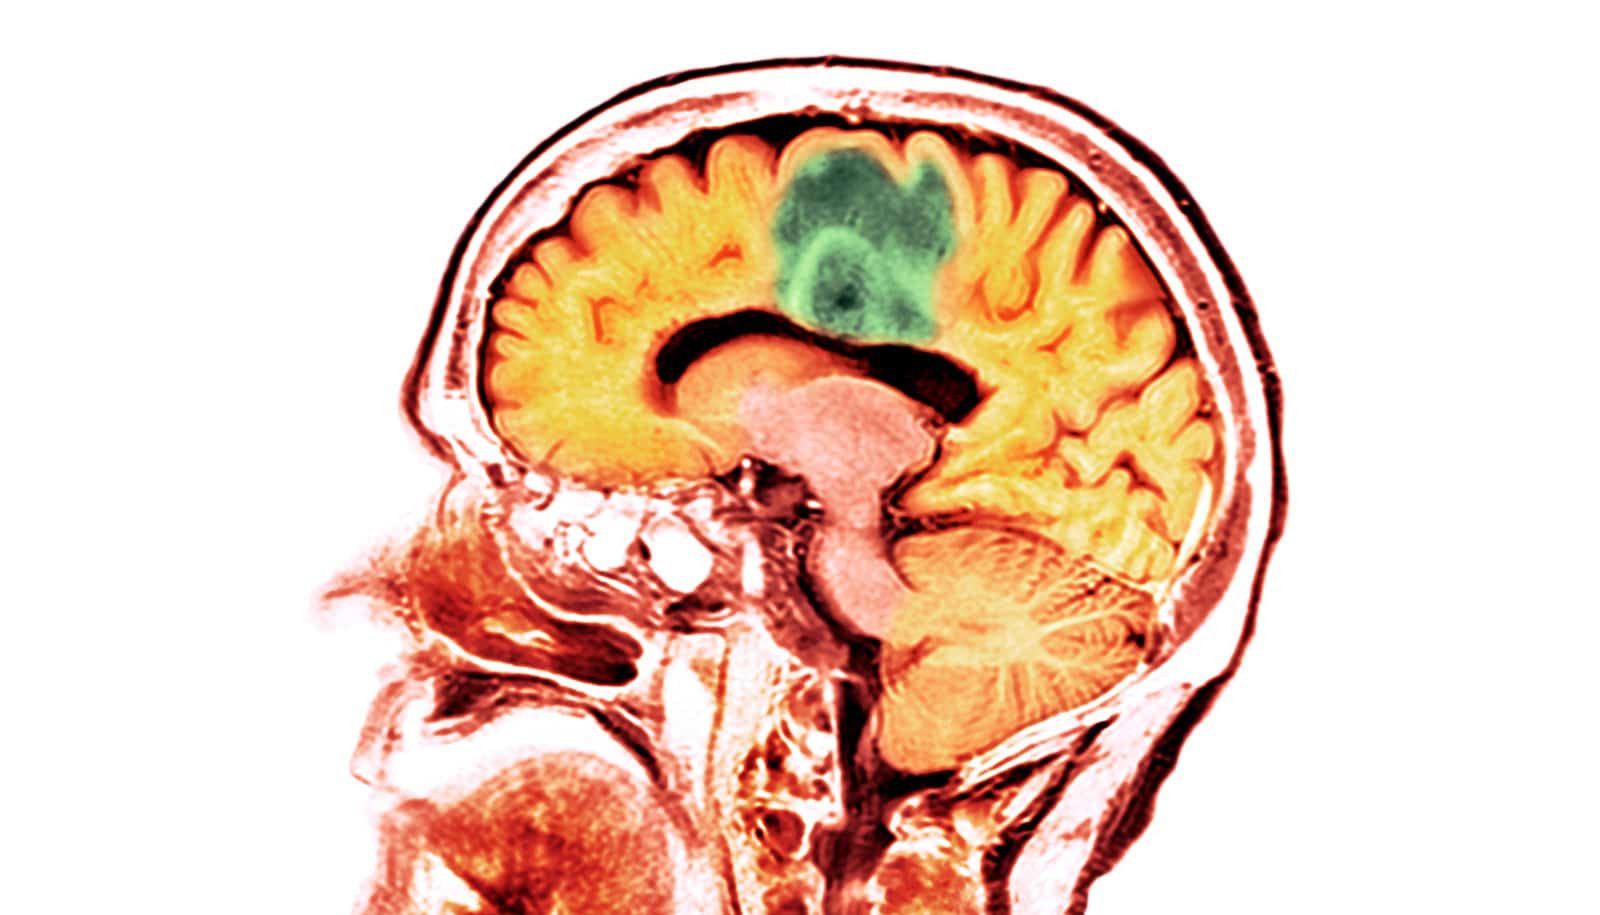

A brand new examine reveals that adults who’ve suffered a moderate-to-severe traumatic mind damage usually tend to develop mind most cancers.

Zafonte’s group examined greater than 150-thousand civilian adults throughout three well being techniques, making this the biggest and most diverse examine to this point a attainable connection between mind tumor improvement and a historical past of TBI. They discovered that whereas sufferers with a gentle TBI weren’t related to a better threat for mind most cancers, sufferers who suffered a reasonable to extreme TBI have been 50% extra prone to develop a malignant mind tumor.

“Why moderate-to-severe TBIs enhance the chance of tumors isn’t well-understood,” Zafonte says. “This could possibly be due to disruptions in metabolic processes or a rise in inflammatory responses within the mind and nervous system.”

These findings might current a chance to determine mind tumors earlier. Sufferers with a medical historical past of a TBI could possibly be screened for tumor development, and the early detection of most cancers would make it way more treatable and consequently enhance affected person outcomes. The examine didn’t distinguish between various kinds of malignant mind tumors, although, and presents a analysis alternative to see if there’s a particular sort linked to TBIs.